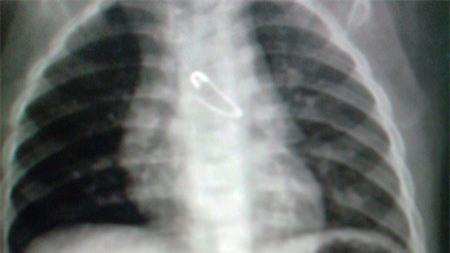

Ngày 16/4, BV Nhi Trung ương cho biết, các bác sĩ của BV này đã thực hiện thành công ca nội soi gắp kim băng trong phế quản cho một bệnh nhi mới 10 tháng tuổi.

Hình ảnh X-quang ngực có kim băng

Bệnh nhân là Lê Anh Th., ở Xuân Lộc (Hà Tĩnh). Theo lời kể của người nhà bệnh nhân, trong lúc ngồi chơi cùng bà và mẹ, cháu Th. nhặt được chiếc kim băng của bà làm rơi và cho vào miệng. Mẹ cháu hốt hoảng dùng tay móc miệng cháu để lấy kim băng ra. Cháu khóc thét và nuốt vật này vào sâu hơn. Lập tức gia đình đưa cháu đến BV tỉnh Hà Tĩnh, kết quả chụp X-quang phát hiện kim băng đã nằm trong lồng ngực của trẻ.

Tại BV Nhi Trung ương, kết quả chụp X-quang ngực thẳng và nghiêng cũng cho thấy có hình ảnh kim băng nằm trong đường thở, tận phế quản góc trái. Đặc biệt, kim băng ở trạng thái mở, đầu nhọn quay lên trên và ngập sâu vào niêm mạc phế quản. Sau khi hội chẩn, các bác sĩ đã quyết định mổ nội soi phế quản để lấy dị vật. Ca phẫu thuật diễn ra trong 2 giờ đồng hồ. Bệnh nhi sau đó đã bình phục, sức khỏe tốt và được xuất viện.